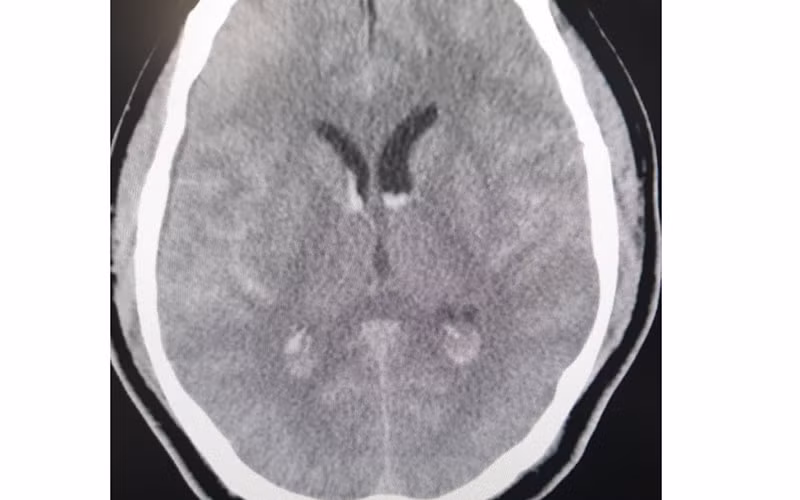

Hình ảnh phim chụp xuất huyết dưới nhện lan tỏa - tụ máu não thất.

Ngay khi tiếp nhận, các bác sĩ Trung tâm Đột quỵ đã nghi ngờ nguyên nhân chảy máu dưới nhện là do dị dạng mạch não. Bệnh nhân được đi chụp CTA - chụp mạch não phát hiện: chảy máu dưới nhện lan tỏa - chảy máu não thất do vỡ phình lóc tách động mạch đốt sống phải đoạn V4. Đây là một tổn thương có vị trí khó, phức tạp và tinh vi, thường cần một bác sĩ chẩn đoán hình ảnh chuyên sâu và nhiều kinh nghiệm mới chẩn đoán được.